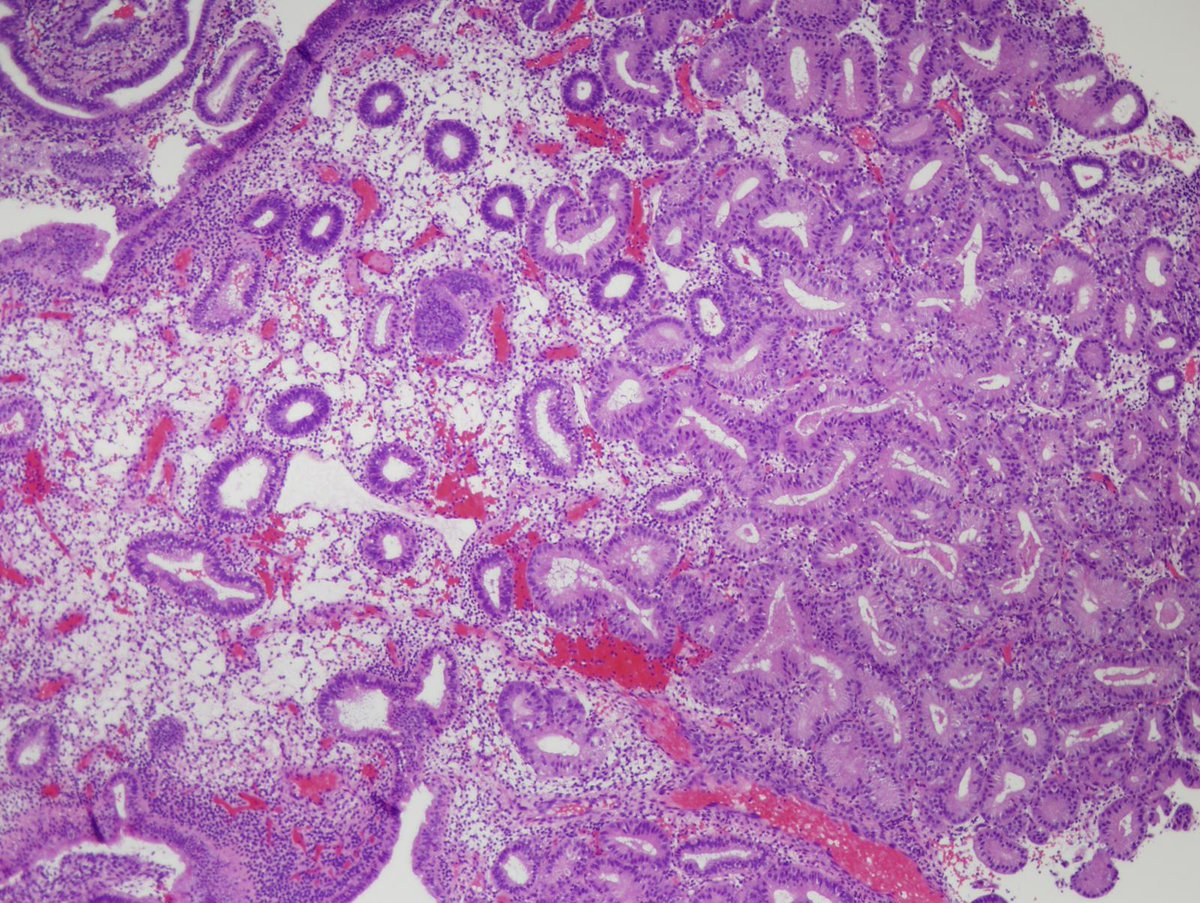

#PathQuiz 🔬

A) Hyperplasia without atypia

B) Hyperplasia with atypia

C) Endometrial polyp

D) Atypical polypoid adenomyoma

#Pathology #GYNPath #Endometrium

Clue in caption 🧐

✅ Endometrial atypical hyperplasia / EIN 🎯

• Defined as a geographical lesion where the glandular volume exceeds the stromal volume.

• Shows significant cytological atypia (loss of polarity, rounded nuclei) distinct from background glands.

• It is a clonal proliferation and a direct precursor to low-grade endometrioid adenocarcinoma.

• Often associated with loss of PTEN or PAX2 expression.